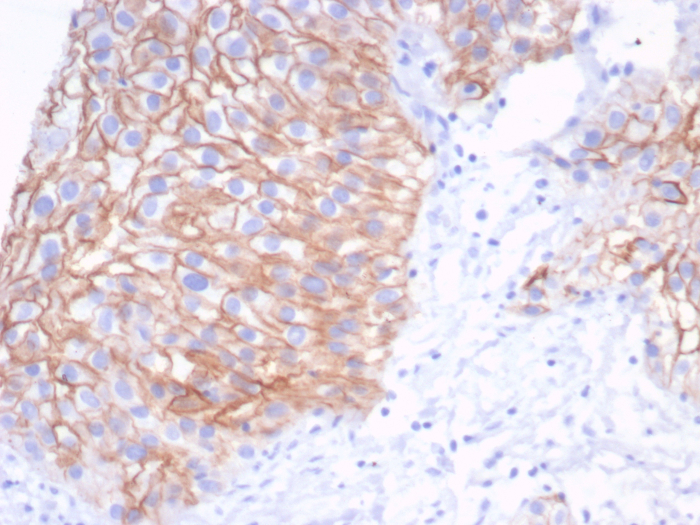

| Applications: | IHC, ICC/IF |

| Reactivity: | Human |

| Details: | Mouse IgG2a Kappa Monoclonal Clone #S100A14/7401 |

![Immunohistochemistry-Paraffin: S100 calcium binding protein A14 Antibody (S100A14/9077R) - Azide and BSA Free [NBP3-24305] -](https://resources.bio-techne.com/images/products/nbp3-24305_rb-s100a14-mab-s100a14-9077r-azide-bsa-free-1312202316331820.jpg)

![Immunohistochemistry-Paraffin: S100 calcium binding protein A14 Antibody (S100A14/9077R) [NBP3-23639] - S100 calcium binding protein A14 Antibody (S100A14/9077R)](https://resources.bio-techne.com/images/products/nbp3-23639_rabbit-s100-calcium-binding-protein-a14-mab-s100a14-9077r-1312202311502947.jpg)